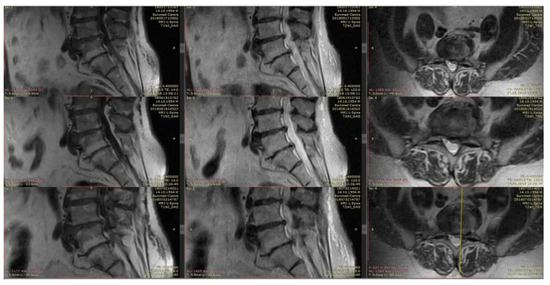

4.3. Clinical Case 2 (L-Aesineate 5 mL Group)

In our opinion, this case needs an additional comment. It is generally considered that an increase in the size of the intervertebral disk hernia is a negative predictor, but the data from numerous publications and observations indicate the opposite. Intervertebral hernia accompanied by sequestration or extrusion, without motor deficiency clinically, is more likely to by reabsorbed and “shrink”. Despite the large size, it is easier to dehydrate and reconfigure them in such a way that they do not create compressions of neuronal structures [59,60].

Patient M., 41, complains of moderate back pain and “striking” pain in the right leg. At the primary examination: excess body weight, neurological status without sensory, reflex, or motor deficiency. VAS: 5 points. Straight leg test right-side to 35°.

MRI: On the background of degenerative-degenerative changes and protrusions, there is a L4–L5 level hernia. At the first control, extrusion of bulging and caudal migration.

It is interesting that the VAS values at the first control was 0 points. In this case, the increase in size and shape changes were an element of sanogenesis: caudally displaced hernia does not compress neuronal structures (Figure 7).

Figure 7. Initial T2-weighted MRI of the lumbar spine shows a large extruded disc at the L4-L5 level and the follow-up imaging shows up migrating fragment.